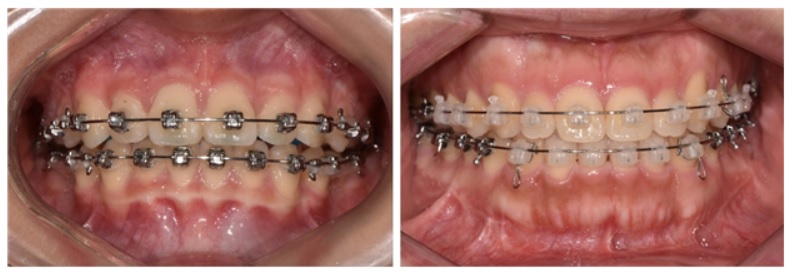

교정치료 기기 브라켓, 금속 브라켓(왼쪽)과 세라믹 브라켓

일반적으로 전체 치아를 배열하는 교정치료는 ‘브라켓’이라는 장치를 치아 바깥쪽에 붙이고 교정용 와이어를 넣어 진행한다. 브라켓은 크게 금속과 세라믹으로 나뉘는데, 금속은 조금 더 튼튼하지만 눈에 잘 띄고 세라믹은 간혹 깨질 수는 있지만 눈에 잘 띄지 않는다는 장점이 있다.